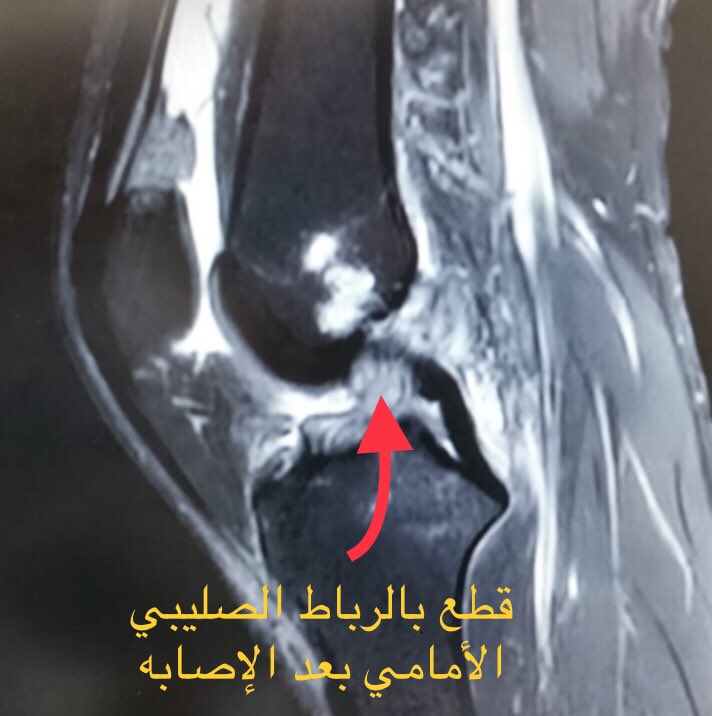

القطع الجزئي للرباط الصليبي الامامي عيادة الركبة و الفخذ